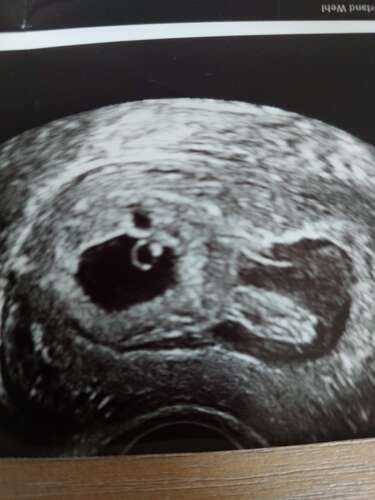

Ik heb ook in het begin van m'n zwangerschap eens een echo gehad na wat bloedverlies (geen grote plassen zoals jij beschrijft) en toen zagen we ook een hele kleine ruimte waar eventueel bloed vandaan kon komen. Maar bij mij was het zo klein dat de echoscopiste er normaal niets van zou zeggen als de moeder geen bloedverlies zou hebben... hopelijk is het bij jou net zo onschuldig als het bij mij was. Ik ben inmiddels 33 weken zwanger van een actief meisje ☺️

Ik had dit ook maar dan echt een hele grote holte met vocht. Mijn verloskun ...

En bij mij zagen ze idd ook een cyste op m'n eerste echo. Overblijfsel van het eitje. Die is daarna netjes uit zichzelf weggegaan. Wellicht dat dat verband met elkaar houdt?